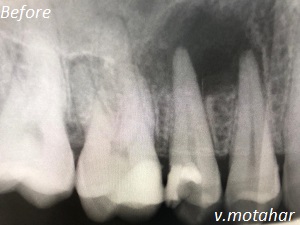

Root canal treatment on three rooted tooth! which had 4 canals!